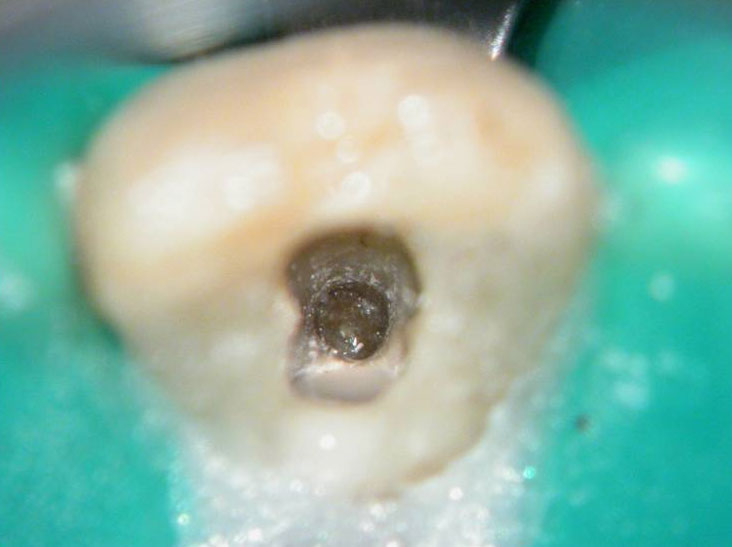

Red arrow shows calcification covering the MB2. Removal of this calcification with ultrasonics reveals the missed MB2(yellow arrow)

5 canals cleaned, shaped and obturated after 10 days of calcium hydroxide. MB1 and MB2 had seperate portals of exit. DB2 merged intoDB1. Palatal two portals of exit.